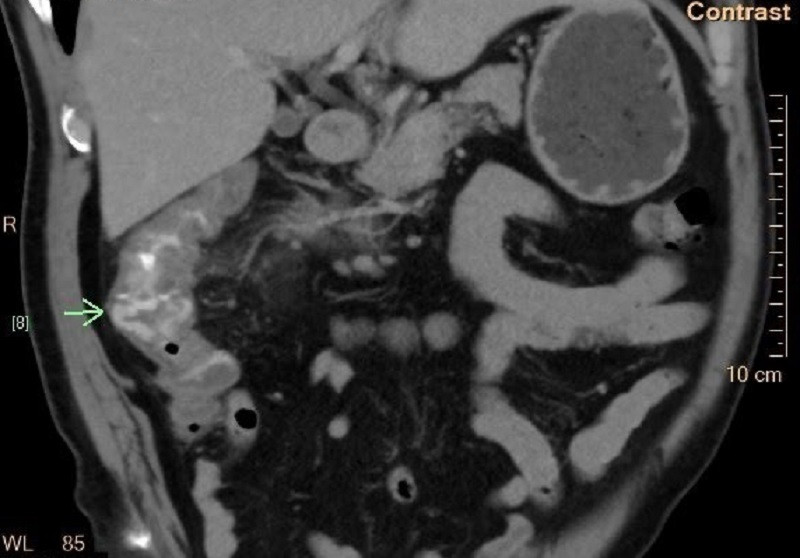

Trước khi nhập viện, bệnh nhân đột ngột đi cầu ra máu ồ ạt, kèm đau vùng bụng bên phải. Sau khi nhập viện cấp cứu, ông được các bác sĩ thăm khám, xét nghiệm máu và chụp cắt lớp (CT) vùng bụng. Kết quả cho thấy, đại tràng phải của bệnh nhân có túi thừa viêm đang xuất huyết mức độ nặng.

| Vị trí túi thừa đại tràng bị viêm gây xuất huyết ồ ạt khiến bệnh nhân mất máu cấp |